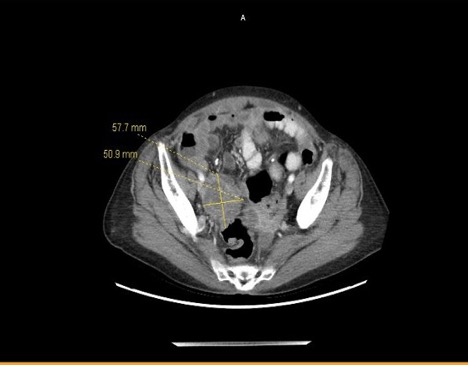

We present an unusual presentation of a chronic appendicular abscess. A 57-year-old presented to the emergency department with acute on chronic abdominal pain, worsening discomfort, abdominal distention and decreased appetite. Abdominal imaging revealed the presence of multiseptated cystic right adnexal mass, concerning for metastatic ovarian carcinoma. Intra-operatively the diagnosis of a likely chronic ruptured appendix at the base of the colon was confirmed.References